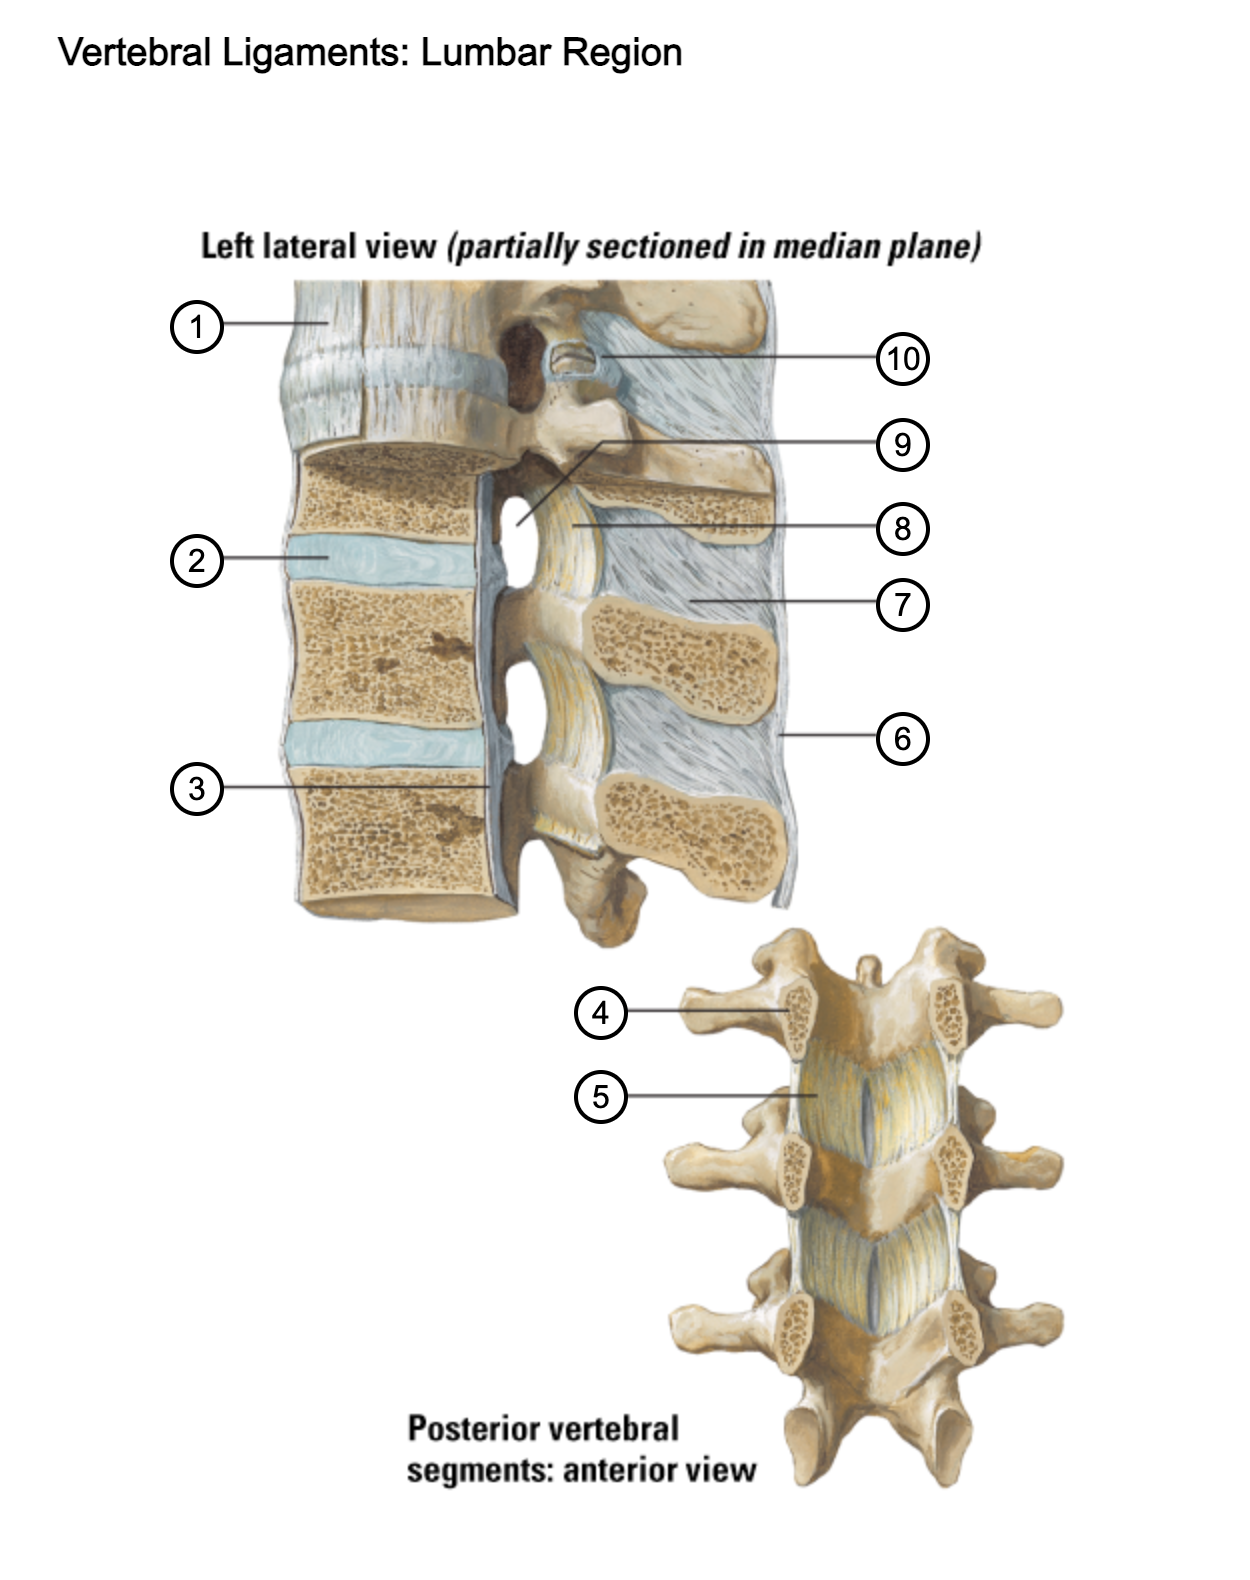

1

anterior longitudinal ligament

2

intervertebral disc

3

posterior longitudinal ligament

4

pedicle (cut surface)

5

ligamentum flavum

6

supraspinous ligament

7

interspinous ligament

8

ligamentum flavum

9

intervertebral foramen

10

capsule of zygapophysial join (partially opened)